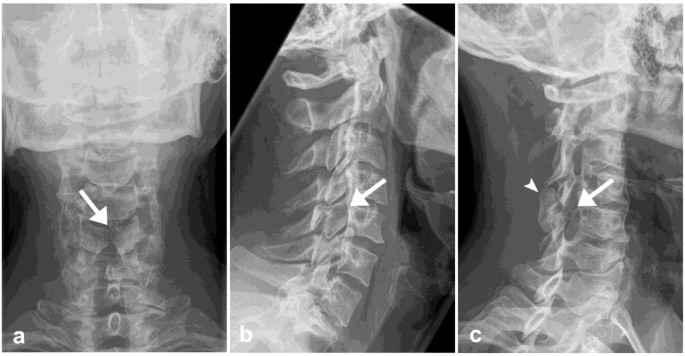

Рентген шейных позвонков при спина бифида

Раздел: Фотозарисовки